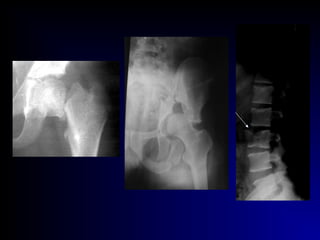

 Pathological fr.:

- general causes : senile osteoporosis

endocrinal diseases:

( hyperparathyroidism, Cushing syndrome)

- local causes : inflammation

tumor

bone cyst, fibrous lesion

Pathological fractures